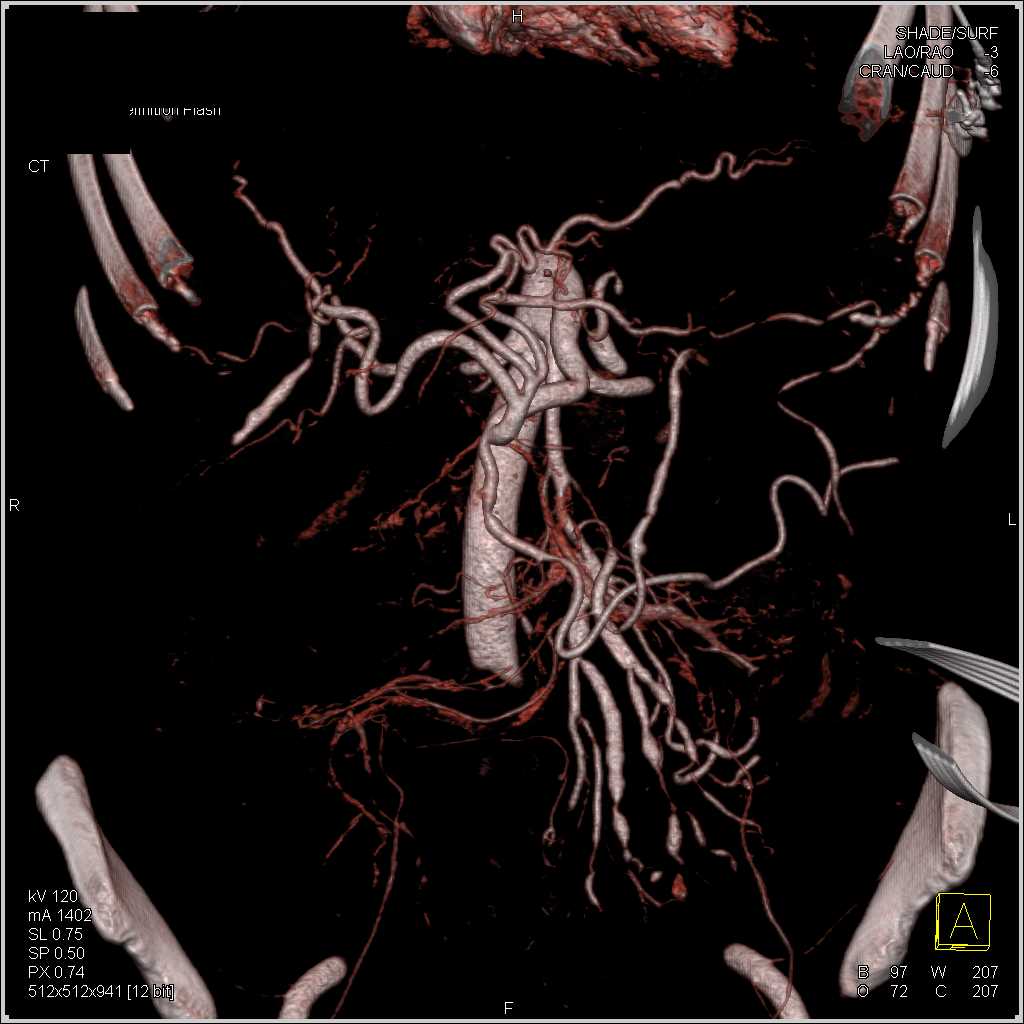

SMA Encasement by Carcinoid Tumor